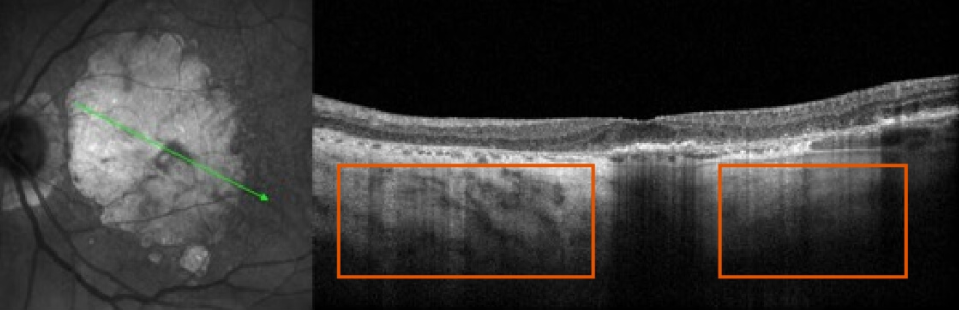

- Patient at baseline has a large area of GA, however, BCVA is relatively unaffected due to foveal sparing

- Within 4 years, OS GA has progressed, but BCVA has only declined slightly as fovea is still intact

BASELINE VISIT

- BCVA: 6/7.5

- Visual function: Patient requires assistance from a caregiver on some activities (eg, cooking, driving), since pericentral vision is lost due to GA

4 YEARS AFTER BASELINE VISIT

- BCVA: 6/15

- Visual function: Although patient maintains relatively good BCVA, she has poor visual quality. Patient relies heavily on caregiver for assistance with many activities of daily living

Although there is significant atrophy, the fovea remains relatively spared from GA.